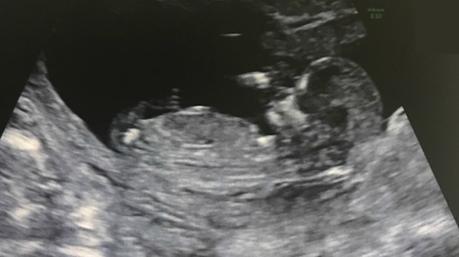

De hecho, late desde antes de que yo siquiera lo sospechara.

Y aunque todavía no haya asimilado que seamos merecedores de vivir un nuevo milagro, ahí está, al otro lado de la pantalla, asegurándome que es cierto.

Si todo va bien, en primavera seremos padres de nuevo.